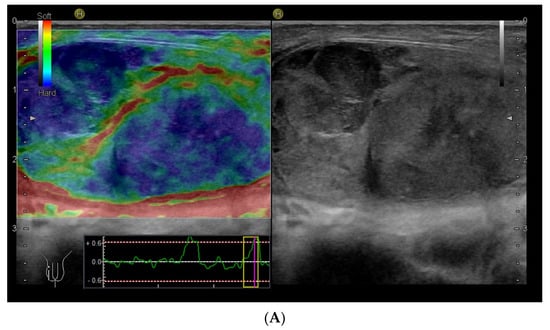

Within the scrotum, the two testicles are divided by a septum. Each testicle is oval-shaped and typically measures 4 cm in length, 3 cm in width, and 2 cm in height [64]. The anatomy of the testicles can be seen in Figure 6C, and an ultrasound image including SE is shown in Figure 6A,B. A high-frequency linear transducer is typically the preferred and best choice, but in cases with an enlarged scrotum, a curved array transducer may be a better choice.

Figure 6.

Ultrasound images of a 39-year-old male. The indication for ultrasound investigation was suspected orchitis or malignancy. The patient experienced pain in the right testicle for more than 2 days. The patient was seen in the emergency room for assessment of epididymitis and started treatment with ciprofloxacin. There was no improvement with treatment, and the right testicle became more tender and swollen. The ultrasound showed no signs of epididymitis (A). The right testicle (left side of the figure shows the elastogram, and B-mode is seen on the right side). The testicle revealed a right-sided tumour, which appeared highly suspicious using elastography (B). The B-mode image, showing a tumour (C). B-mode image of the left testicle, showing normal tissue (The pathology showed a seminoma testicular tumour with 2% of choriocarcinoma. The patient underwent surgery for removal of the right testis.